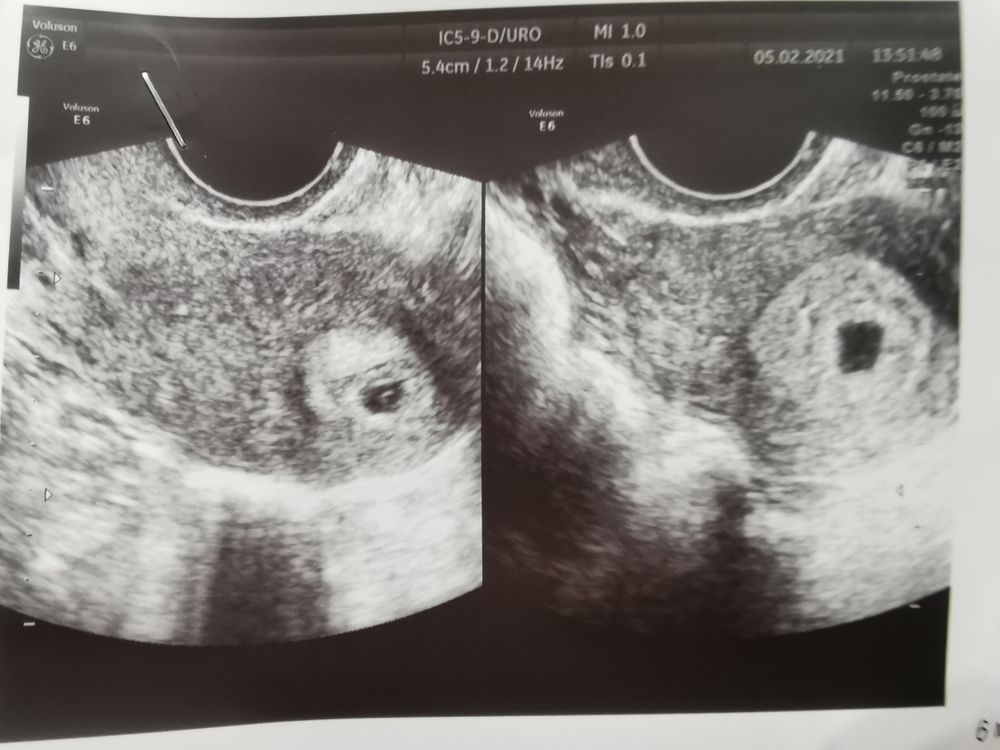

Девочки у кого есть Фото узи двойни на ранних сроках

кому не сложно поделитесь фото с УЗИ двойней на ранних сроках буду благодарна!